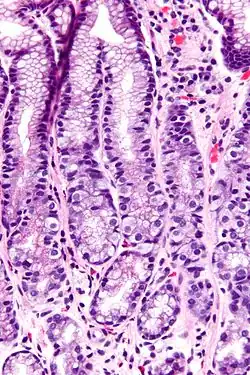

A célula G é um tipo de célula do antro gástrico, parte afunilada do estômago, que secreta gastrina, hormônio protéico liberado na ingestão de alimentos com alto teor protéico. Atua na mucosa gástrica estimulando células parietais a liberarem HCl.[1]